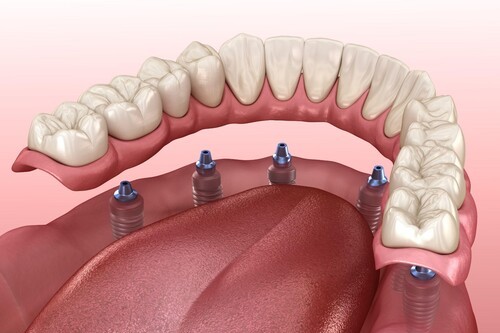

インプラントオーバーデンチャー

顎の骨に埋め込んだ数本のインプラント(人工歯根)を土台として利用し、総入れ歯などの比較的大きな入れ歯を安定させる方法です。

インプラントに連結されたアタッチメントと入れ歯側の装置によって固定されるため、入れ歯がずれにくく、しっかりと噛むことができます。アタッチメント義歯と同様に、ご自身で簡単に取り外してお手入れすることも可能です。